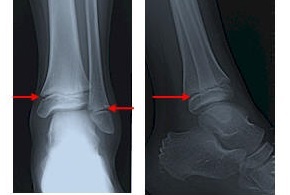

骨の端にはこれから骨になるよ〜っていう通常よりも柔らかい軟骨があります。成長軟骨とも呼ばれていますがレントゲンで診てみると線が入っているように見えることから骨端線と呼ばれています。

そしてこの骨端線の長さでどれだけ身長が伸びるのかがわかります。

骨端損傷とは?

成長軟骨はとても柔らかく強い力が加わると簡単にズレや変形にもなりやすく放置すると後遺症として成長閉鎖や変形による歩行困難にもなる可能性があります。

そう簡単には損傷は起きないのですが、例えば強い力が斜め方向からくる場合や体重がかかった状態で地面に膝をついたりするとズレが起きやすくなります。

今回も運動中に人とぶつかり床に強打して足を動かすと痛みが出て、普通に歩く際にも痛みがある状態でした。

このままですと骨の変形と成長が止まる可能性がある為ギプスシーネで固定し整形外科へ紹介状を書き行って診断をしていただいてます。